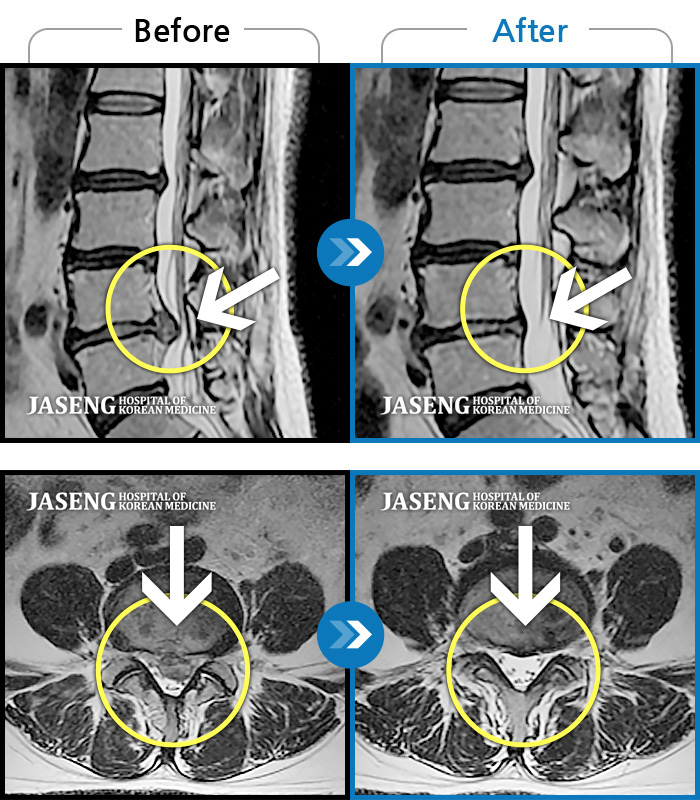

허리디스크

안산 · 김민수 원장

발목의 힘이 떨어져서 절뚝거리면서 걸었다.

촬영시기

2022.01.03 ~ 2024.07.31

2024.08.09

조회수 518